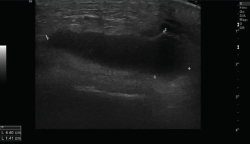

2.2. Roturas

Se observan áreas hipoecoicas de solución de continuidad de las fibras tendinosas(7), con retracción de los márgenes con la contracción muscular cuando la rotura tendinosa es completa (Figuras 9 y 10).

Figura 9. Corte sagital de una ecografía de rodilla: foco hipoecoico por rotura parcial del tendón cuadricipital.

Figura 10. Corte sagital de una ecografía de rodilla: ausencia del tendón rotuliano por rotura completa, con hematoma señalado en el trayecto del tendón.